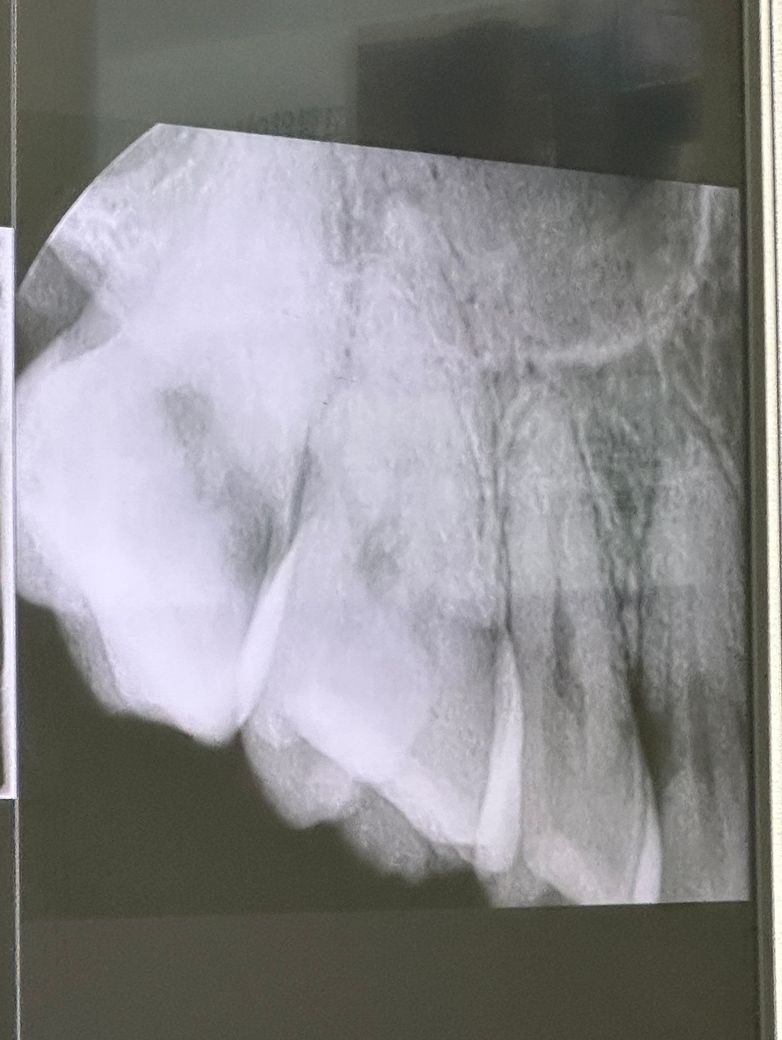

치주인대 늘어남 or 인접면 충치인지 궁금합니다

3주전쯤 오른쪽위 끝 어금니쪽에 치실 워터픽으로 자극을 너무 세게한날 아파서 치과에갔는데 이상없다고 했는데 아직 통증이 남아있어 파노라마사진을 다시찍었는데 사진상으로 볼때 인접면충치일수도 있나요?? (첨부:이틀전 파노라마사진)

인접면에 충치가 있어보이지는 않습니다. 자극에 의한 증상일 가능성이 높아보이고 좀 더 지켜보시는게 좋겠습니다.

엑스레이 상에 어금니 사이에 방사선 투과상이 관찰되는거 보아서는 인접면에 충치가 있어 보이긴합니다.